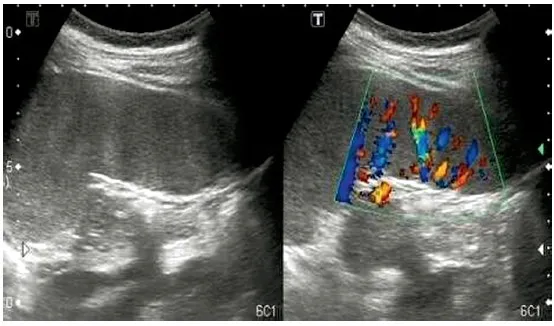

USG jamy brzusznej dlaczego to podstawowe badanie obrazowe?

Ultrasonografia (USG) jamy brzusznej jest nieinwazyjnym i szeroko dostępnym badaniem, które pozwala na ocenę wielkości, kształtu i struktury nerek. Dzięki USG lekarz może wykryć kamienie nerkowe, torbiele, wodonercze, a także ocenić, czy nerki nie są powiększone lub zmienione w swojej budowie. Jest to zazwyczaj pierwsze badanie obrazowe zlecane w przypadku podejrzenia problemów z nerkami.